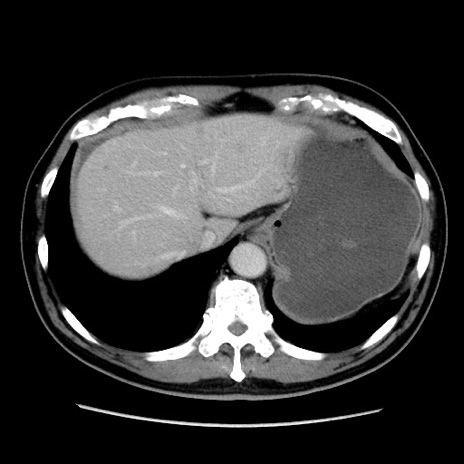

症例16(横断像)

【症例】 70歳代男性

【主訴】 腹痛、嘔吐

【現病歴】 約1ヶ月前より間欠的に腹痛と嘔吐あり、当院消化器内科を受診したところCTで多発する肝臓のLDAを指摘され、精査中であった。以降は消化器症状は安定していたが、2日前より嘔気と腹痛があり、同日より排便・排ガスが消失した。改善認めず、 本日、救急外来を受診した。

【既往歴】 大腸ポリープ切除後。

【身体所見】意識清明・会話良好、BT 36.3℃、BP 127/80mmHg、 P 80bpm、腹部:膨満あり、平坦・軟、上腹部正中および下腹部正中に圧痛あり、反跳痛なし、筋性防御なし。

【データ】WBC 7200、CRP 0.77